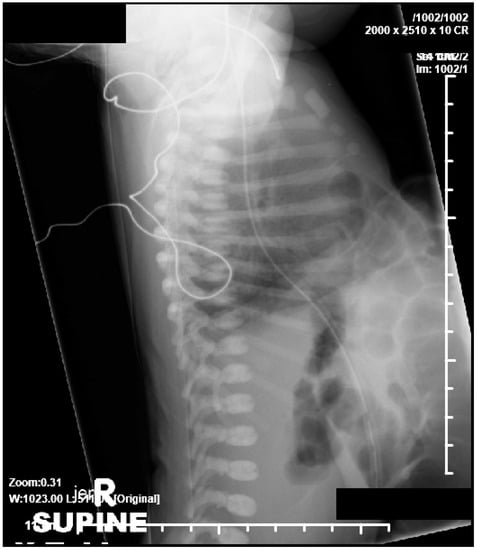

2.1. Case 1